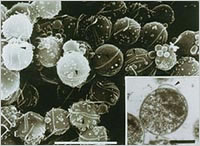

ピロリ菌は3~4本の鞭毛を持った、らせん型の細菌です。胃液の中は強い酸性の塩酸があるため、細菌は棲めないと考えられていました。1983年にオーストラリアのロビン・ウォレンとバリー・マーシャル(2005年ノーベル医学生理学賞受賞)によって胃の粘膜から発見されました。ピロリ菌はアンモニアを作り出すことができるため、自分の周りを中性に近い環境にすることが可能となり、生きてゆくことができるわけです。感染経路は経口感染と考えられています。

ピロリ菌電子顕微鏡写真

(北海道大学大学院医学研究科 病態内科学講座消化器内科学 斎藤永仁博士より供与)

spiral-shaped form

coccoid form

※通常は左図のらせん形の鞭毛(ベンモウ)をもつ桿菌であるが、悪条件下では球形で生存できる特徴がある。